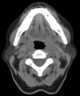

Tonsil and adenoid hypertrophy

Adenoid hypertrophy (enlarged adenoids) is the unusual growth (hypertrophy) of the adenoid (pharyngeal tonsil) first described in 1868 by the Danish physician Wilhelm Meyer (1824–1895) in Copenhagen. He described a long term adenoid hypertrophy that will cause an obstruction of the nasal airways. [Source: Wikipedia ]